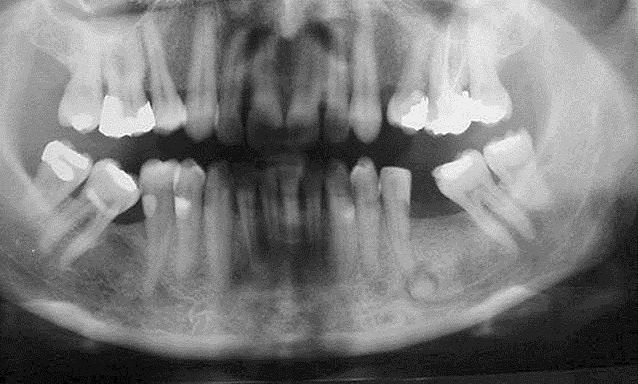

Radiographically, the lesions appear as multiple sclerotic masses in the tooth-bearing regions which usually affect the mandible on both sides in a symmetrical manner, but all four quadrants may be involved, it presents as multiple radiopaque lesions that fuse into lobulated sclerotic masses.

In this case report an FCOD is presented, which is located between the first premolar and the second molar on the left side mandible of a year-old female patient. Abstract Introduction Florid cemento-osseous dysplasia is one of the terms that have been designated by the World Health Organization as cemento-osseous dysplasias of the jaws.

Case report A case of asymptomatic uncomplicated florid cemento-osseous dysplasia occurring in a year-old Jordanian female is reported, which can be considered rare regarding race distribution.

Expansive focal cemento-osseous dysplasia. Clinical, radiographic, biochemical and histological findings of florid cemento-osseous dysplasia and report of a case. Florid COD is characterized by multifocal involvement of the jaw. A year-old Jordanian female patient attended the periodontal clinic at King Hussein Medical Centre in for periodontal assessment.

Minor radiolucency could be recognized around the roots while the high dense deposit within the bone is obvious at the mandibular associated lesions. Intraoral examination showed that the maxilla was completely edentulous; the mandible contained only six teeth: This evolution may take months or years, and during its development, the diameter of the lesion increases from 0.

A complete or partial radiolucent dyslpasia was noted in a few reports 12,13,22 and a sclerotic border has been less frequently reported 2,14,22 Fig. None of her family reported to have similar conditions. Clinical, radiographic, and histological findings of florid cemento-osseous dysplasia: Of the patients for whom age and sex were known, the majority 97 [ In this retrospective analysis, COD more usually occurs in the mandible, both in tooth-bearing and edentulous areas, but may occasionally occur in the maxilla.